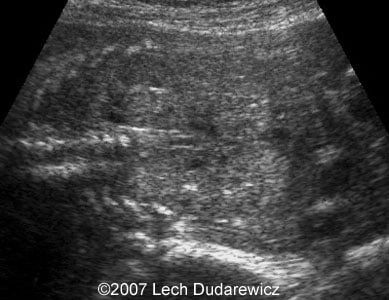

Here are some second trimester ultrasound images of anhydramnios caused by autosomal recessive polycystic kidney disease.

Images 1, 2: Coronal planes through the fetal kidneys with echogenic parenchyma.